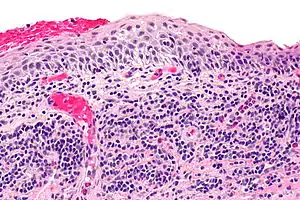

| Micrograph of plasmacytosis mucosae. H&E stain. | |

Balanitis plasmacellularis is a cutaneous condition characterized by a benign inflammatory skin lesion characterized histologically by a plasma cell infiltrate.[2]: 657 [3]